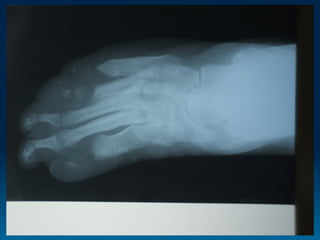

HALLAZGOS GENERALES EXTREMIDADES: NEIUROPATÍA SENSITIVA, ULCERAS PLANTARES,SOBREINFECCION; PARALISIS CUBITAL Y PERONEA , ARTICULACIONES DE CHARCOT NARIZ: CONGESTION NASAL CRONICA, EPISTAXIS, SILLA DE MONTAR OJOS:PARALISIS DE NERVIOS CRANEALES , LAGOFTALMOS, AUSENCIA DE SENSIBILIDAD CORNEAL. EN LL GLAUCOMA, UVEITIS, CATARATA TESTICULOS , HIPOGONADISMO LL AMILOIDOSIS SECUNDARIA CON ALTERACIONES RENALES Y HEPATICAS

EVOLUCION Y PRONOSTICO TRAS LA TERAPIA FARMACOLOGICA EL MAS DIFICIL ALTERACIONES SECUNDARIAS A DEFICITS NEUROLOGICOS, CONTRACTURAS Y ALTERACIONES TROFICAS DE MANOS Y PIES. EQUIPO MULTIDISCIPLINAR LAS LEPRORREACCIONES TIPO I1TRANSITORIAS LAS LEPRORREACCIONES TIPO 2. SE PUEDEN COMPLICAR

EVOLUCION Y PRONOSTICOTRAS LA TERAPIA FARMACOLOGICA EL MAS DIFICIL ALTERACIONES SECUNDARIAS A DEFICITS NEUROLOGICOS, CONTRACTURAS Y ALTERACIONES TROFICAS DE MANOS Y PIES. EQUIPO MULTIDISCIPLINAR LAS LEPRORREACCIONES TIPO I1TRANSITORIAS LAS LEPRORREACCIONES TIPO 2. SE PUEDEN COMPLICAR